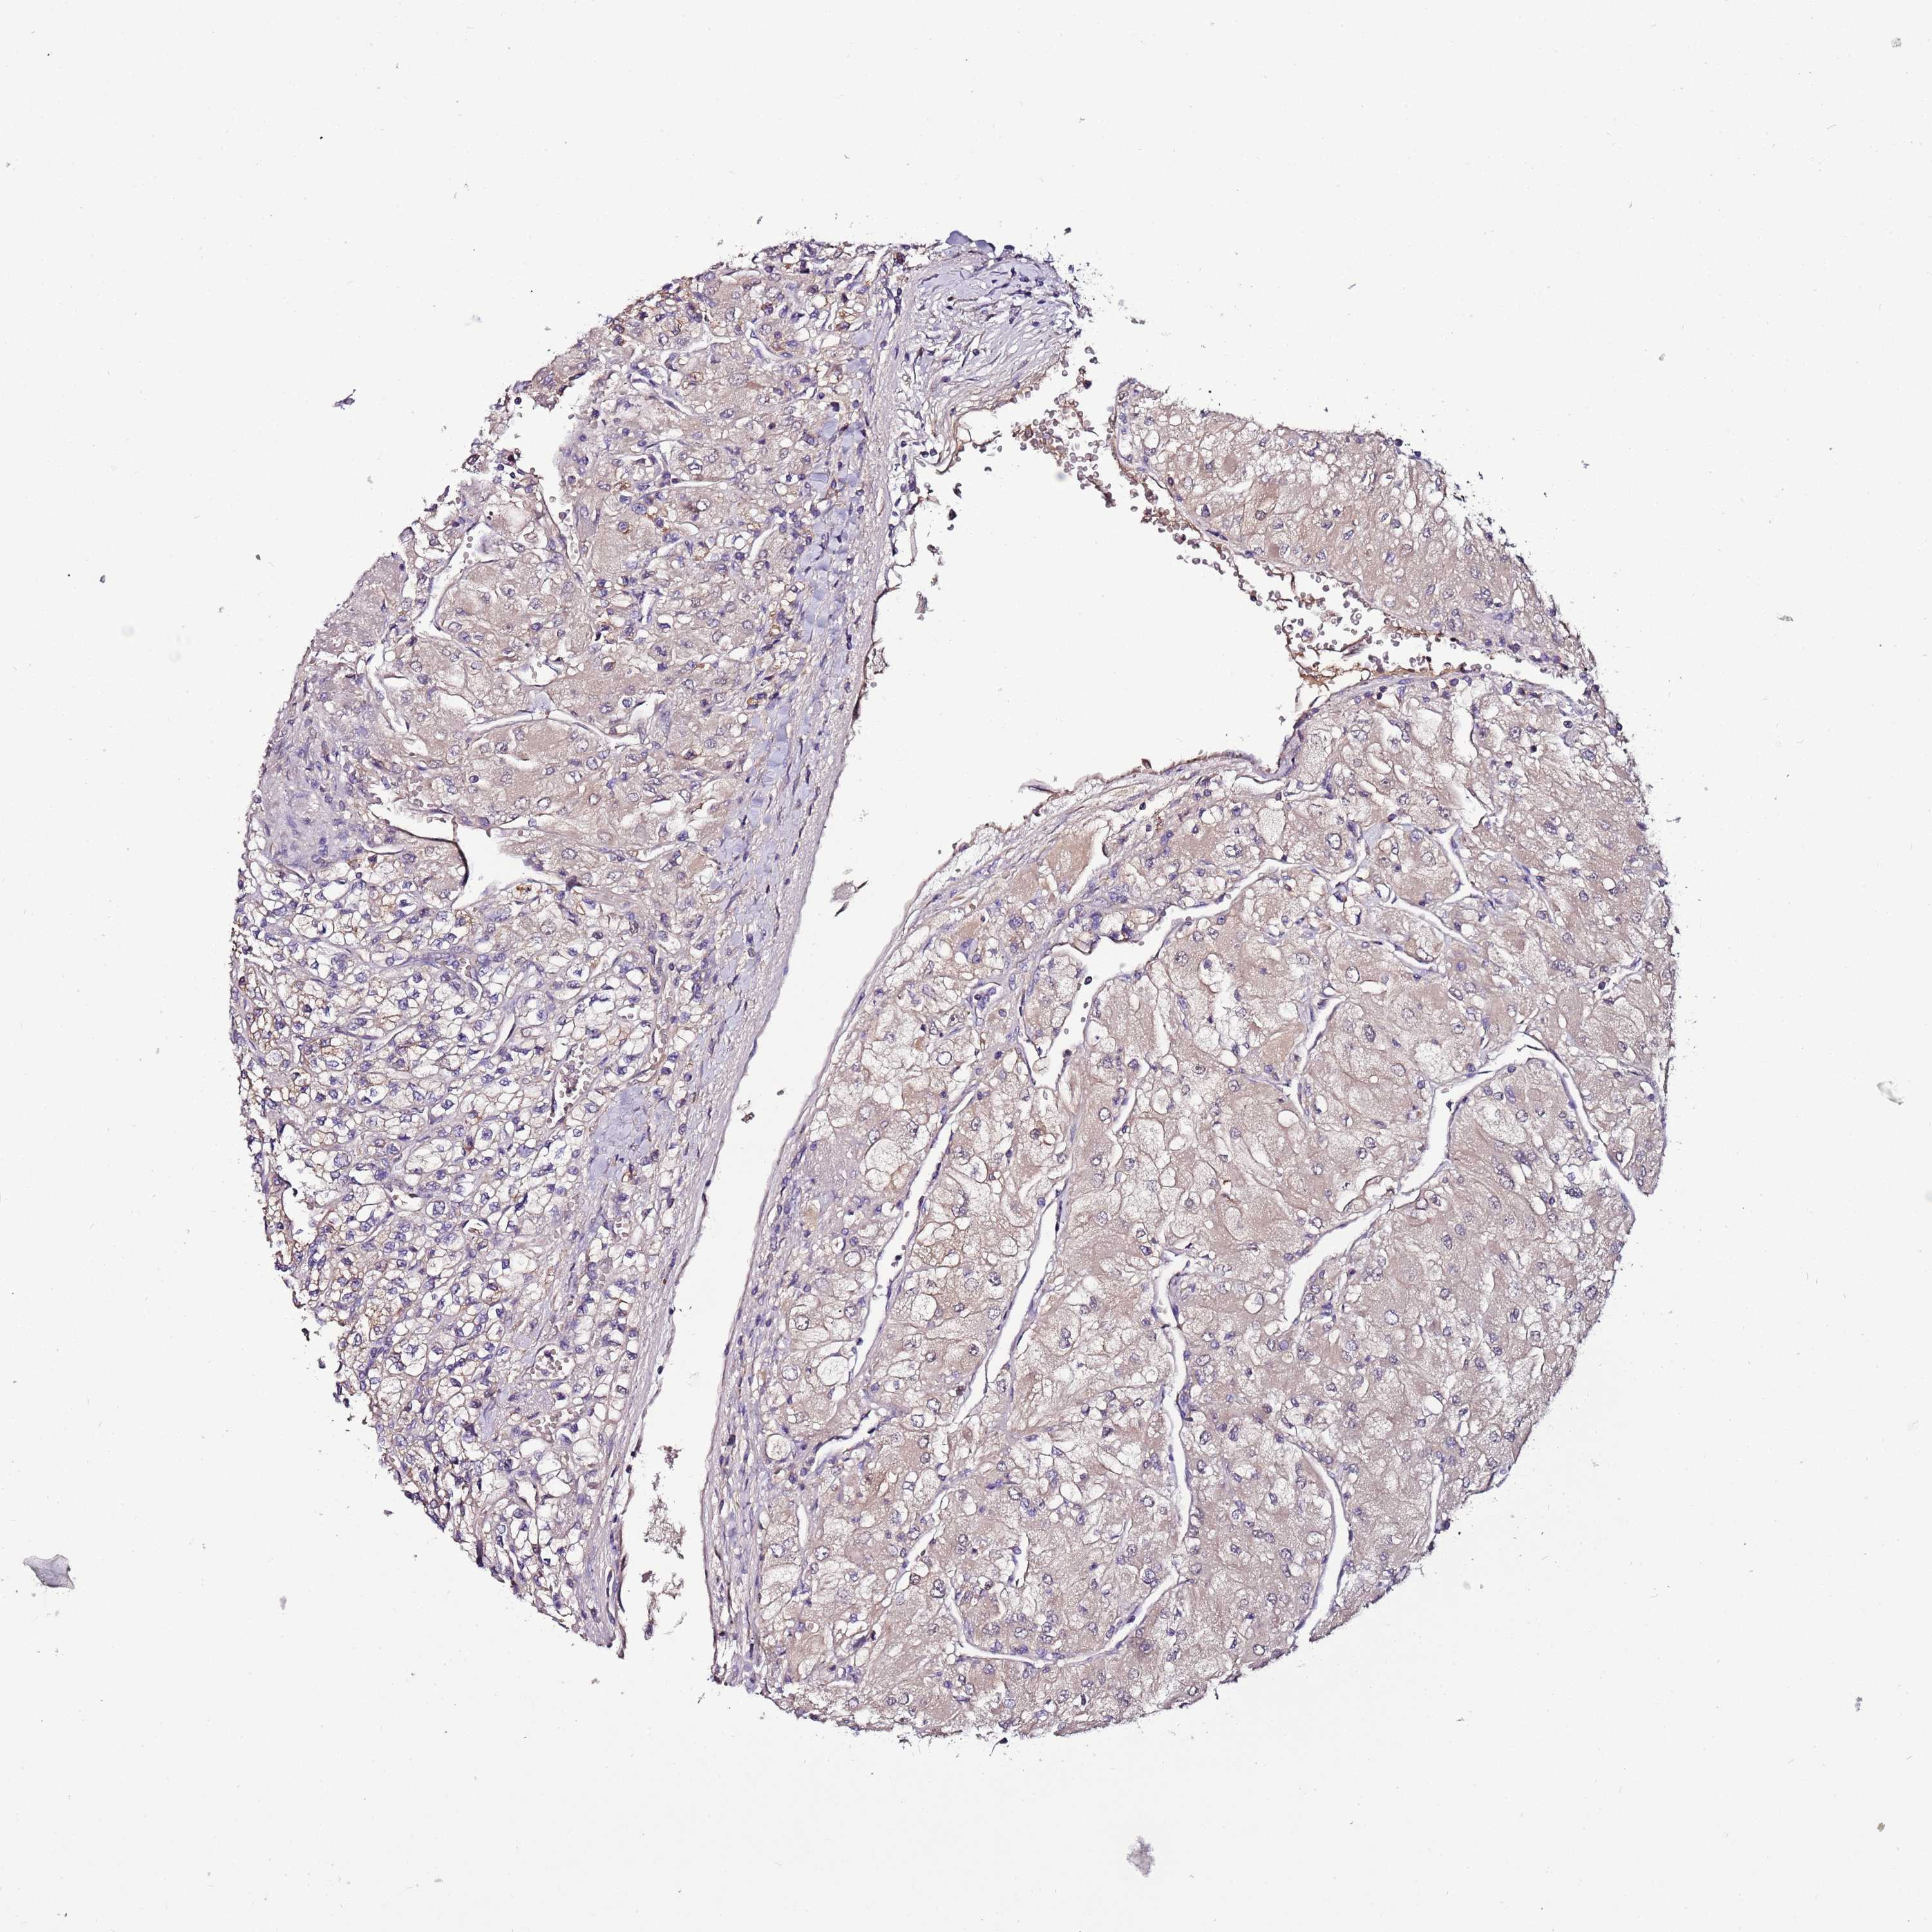

KIDNEY RENAL CLEAR CELL CARCINOMA (VALIDATION) - Interactive survival scatter ploti

The Survival Scatter plot shows the clinical status (i.e. dead or alive) for all individuals in the patient cohort, based on the same data that underlies the corresponding Kaplan-Meier plots. Patients that are alive at last time for follow-up are shown in blue and patients who have died during the study are shown in red.

The x-axis shows the expression levels (FPKM) of the investigated gene in the tumor tissue at the time of diagnosis. The y-axis shows the follow-up time after diagnosis (years). Both axes are complimented with kernel density curves demonstrating the data density over the axes. The top density plot shows the expression levels (FPKM) distribution among dead (red) and alive patients (blue). The right density plot shows the data density of the survived years of dead patients with high and low expression levels respectively, stratified using the cutoff indicated by the vertical dashed line through the Survival Scatter plot. This cutoff is automatically defined based on the FPKM cutoff that minimizes the p-score. The cutoff can be changed by dragging the vertical line or by entering a cutoff value in the square labeled "Current cut-off".

Under the Survival Scatter plot the p-score landscape (black curve; left axis) is shown together with dead median separation (red curve; right axis). Dead median separation is the difference in median mRNA expression between patients who have died with high and low expression, respectively. It is calculated as follows: median FPKM expression of dead patients with high expression - median FPKM expression of dead patients with low expression. This is intended to aid the user in visually exploring custom cutoffs and the associated p-scores and dead median separation.

Individual patient data is displayed and can be filtered by clicking on one or more of the category buttons on the top of the page. Categories describing expression level and patient information include: high, low, alive, dead, female, male and tumor stages. The scale of the x-axis can be toggled between linear and log-scale by clicking on the "x log" button. Mouse-over function shows TCGA ID, patient information and mRNA expression (FPKM) for each patient.

& Survival analysisi

Kaplan-Meier plots summarize results from analysis of correlation between mRNA expression level and patient survival. Patients were divided based on level of expression into one of the two groups "low" (under cut off) or "high" (over cut off). X-axis shows time for survival (years) and y-axis shows the probability of survival, where 1.0 corresponds to 100 percent.

IGIP is validated prognostic, high expression is favorable in Kidney Renal Clear Cell Carcinoma (validation)

: 7.59

Average pTPM 9.4

Number of samples 100